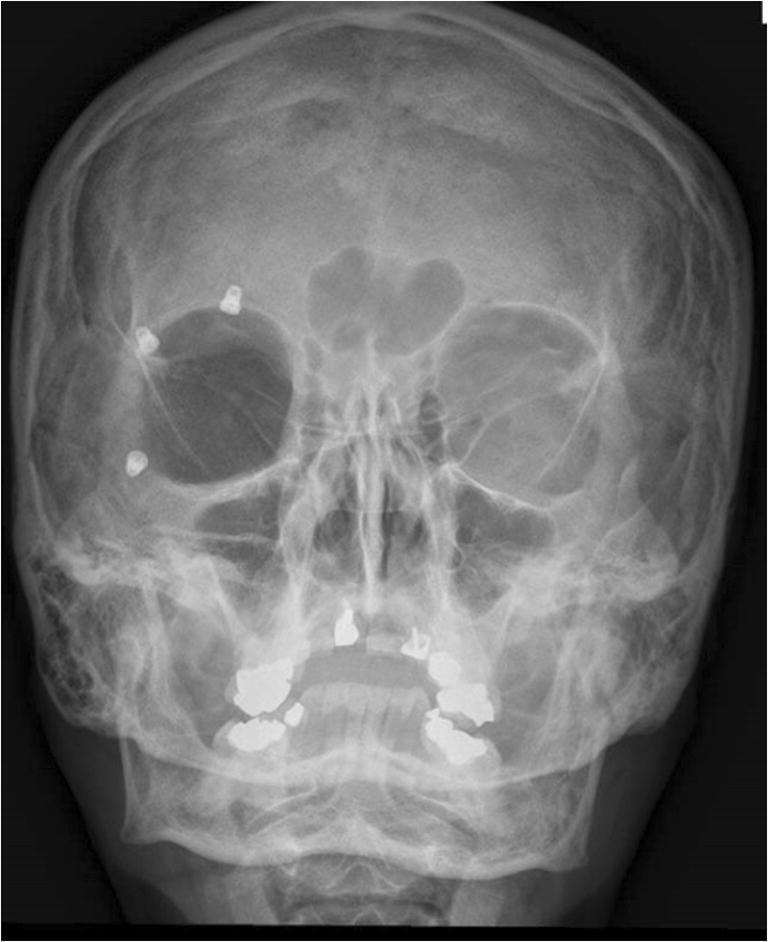

眶周坏死性筋膜炎:从发病到重建历程

Necrotizing fasciitis of the periorbital region: from presentation to reconstructive journey.

Periorbital necrotizing fasciitis is a very rare condition with a UK incidence of 0.24 cases per million per annum. Outcomes can range from disfigurement to sight loss and even death. Debridement is crucial when sight or life is threatened and the subsequent reconstructive stages can be challenging. We describe two cases of periocular necrotizing fasciitis demonstrating the progression of the disease as well as the surgical debridement for both pre-septal and post-septal disease and the reconstructive steps leading to outcome. Level of evidence: Level V, therapeutic study.

眶周坏死性筋膜炎是一种非常罕见的病症,在英国每年的发病率为百万分之0.24例。其后果可能从毁容到视力丧失甚至死亡。当视力或生命受到威胁时,清创术至关重要,而随后的重建阶段可能具有挑战性。我们描述了两例眼周坏死性筋膜炎病例,展示了疾病的进展情况以及针对眶隔前和眶隔后疾病的手术清创术以及导致最终结果的重建步骤。证据级别:V级,治疗性研究。